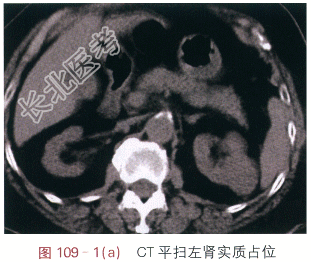

影像学资料如图109-1(a~g)所示。

读片分析:图109-1(a)示CT平扫时左肾中部见一肿块,大小约3.4cm×2.9cm,致左肾局部隆起,肿块密度均匀,CT值约为19.9Hu;图109-1(b)示增强后动脉期肿块明显强化,强化不均匀,平均CT值约为141.0Hu;图109-1(c)示增强后静脉期肿块强化减弱,平均CT值约为104.1Hu。图109-1(d~g)为同一患者MRI图像,图109-1(d)示T₁WI平扫肿块呈等低信号,图109-1(e)示T₂WI肿块呈等高信号灶,信号不均匀,肿块边界清晰,边缘有包膜,图109-1(f)示增强后T₁WI动脉期肿块明显强化,强化不均匀,图109-1(g)示增强后静脉期肿块强化减弱,呈相对稍低信号灶。患者诊断为左肾透明细胞癌。